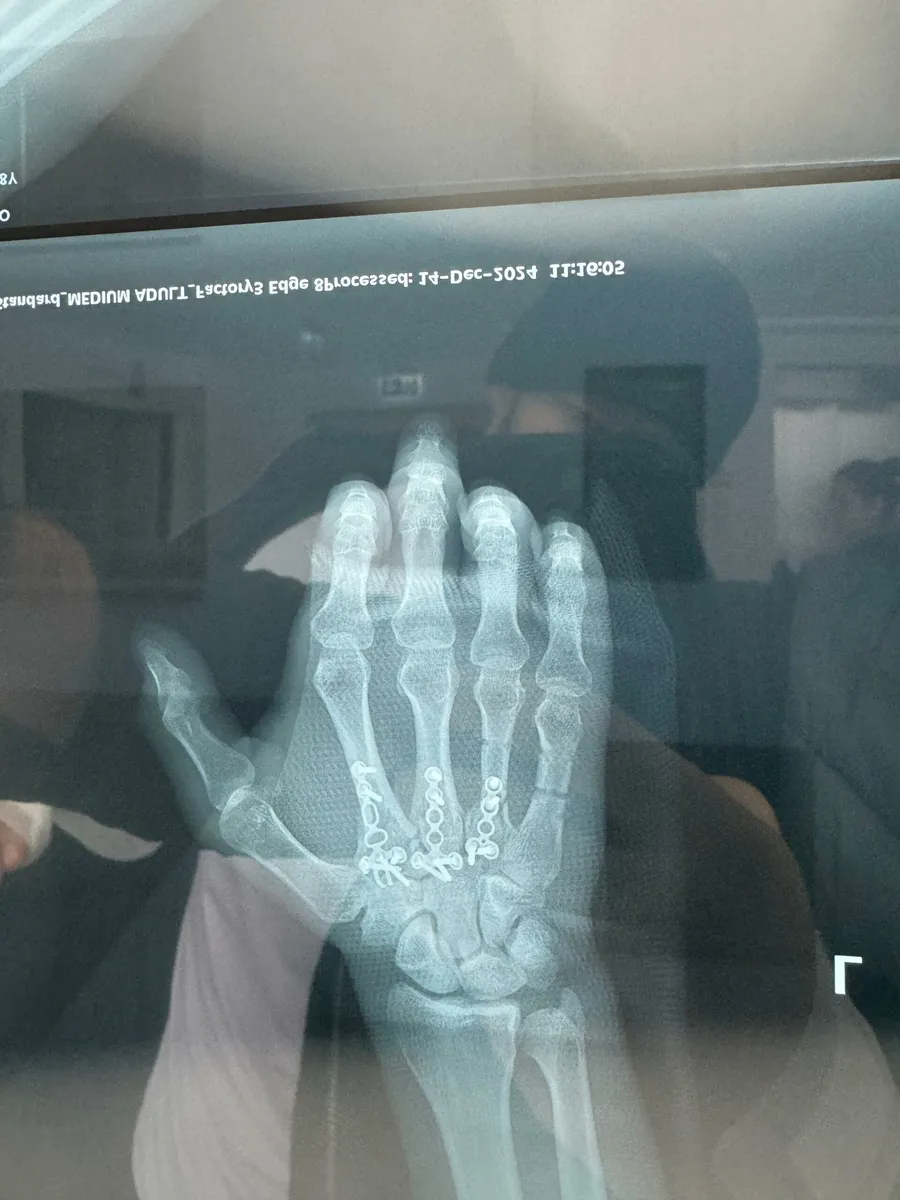

Radiografia mâinii lui Yamato Zaharia, după lupta cu Neveu

„Diagnosticul a fost unul foarte clar, pe care l-am bănuit și în timpul meciului, am degetele 2, 3 și 4 fracturate de la bază. Ele la radiografie nu se mai vedeau, s-au rupt și erau duse spre antebraț. Am fost la medici și am cerut mai multe păreri, până la urmă m-am duc la domnul doctor care m-a operat și la picior, pentru că am foarte mare încredere în el. Mi-a făcut un plan de operație, mi-a montat o extensie prinsă de mână cu o tijă metalică și și-a dat seama în timpul operației că degetele tot nu stăteau la locul lor. Mi-a pus 3 plăcuțe și vreo 14 șuruburi. Toată distracția m-a costat destul de mult, aproximativ 30.000 de lei. Apoi va trebui să mai fac CT-uri, controale, analize, iar în total mă va duce la 35.000 de lei, o sumă destul de mare. Momentan sunt cu mâna în atelă, pentru a nu se bloca din cauza plăcuțelor de titan, e o perioadă destul de dificilă, dar voi trece și peste asta.